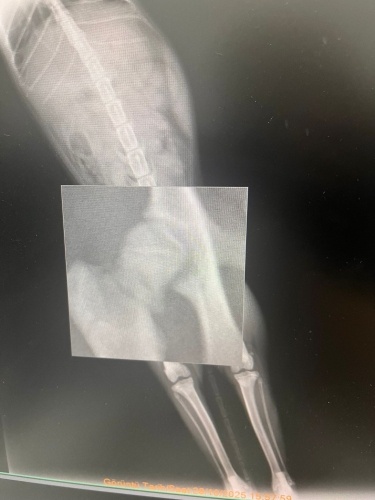

Merhabalar, sekiz aylık kedimin yüksekten düşme sebebiyle sağ arka bacagı kırıldı. Veterinerimiz bir haftalık kafes istirahati ve kalsiyum takviyesi ile kayanayabilecegini söyledi. Hem genç oldugu için hemde kırık çok ayrılmadıgı için. Kalsiyum kaici kedi yogurdu, vitamin malt, kemik iliği suyuyla destekliyorum. Ödül mamalarını falan reddetmiyor mamasını da yiyor ama suyun yüzüne bile bakmıyor. Kaşıkla diline bırakıyorum öyle içiyor. Başına gelen var mı bilmiyorum ama hem kırıkla ilgili yorum hemde su konusunda tavsiyesi olan var mıdır? Fotograf ekliyorum